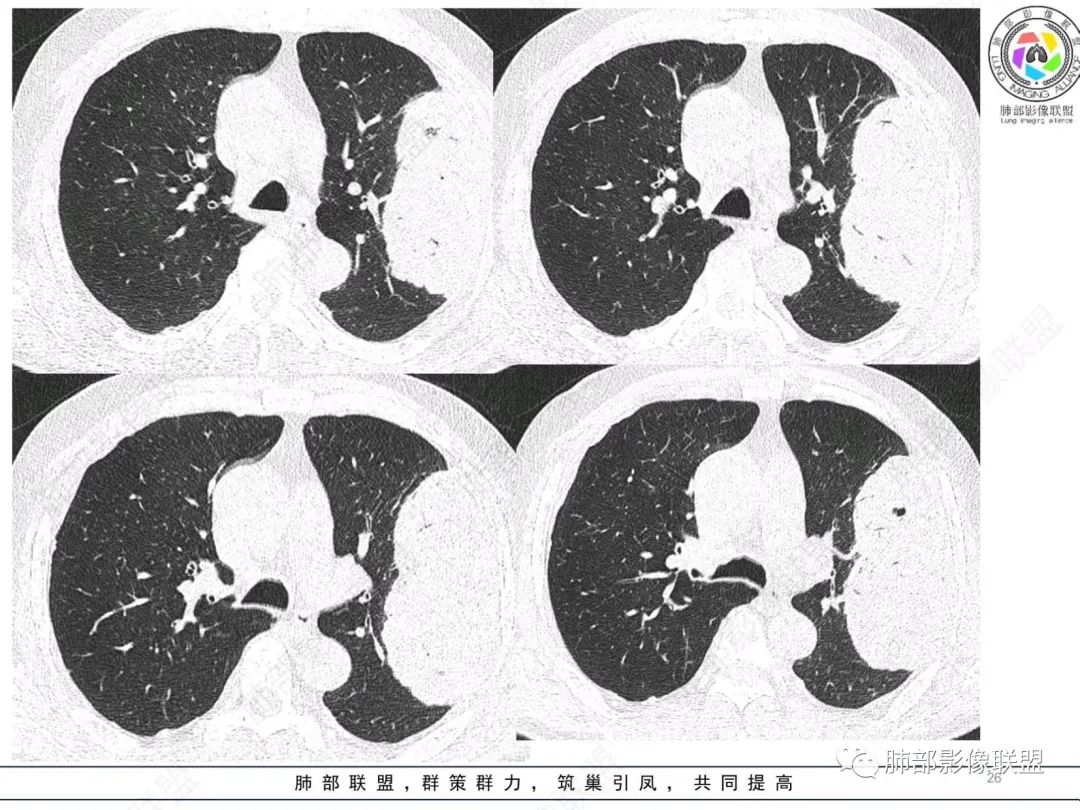

左肺上叶大肿块,膨胀性生长,边界清,密度较低,见部分坏死区,强化弱,肿块见支气管充气V扩张征,分布僵直,枯树枝特点,另一个重要特点血管造影征,淋巴瘤,肿块长轴与胸膜平行,与隐球菌鉴别,隐球荚膜抗原检查,明确诊断经皮肺穿刺。另胸膜钙化(问诊既往有无患胸膜炎病史)。

如果粘液腺Ca,周边太干净了,不支持。

左肺上叶胸膜下肿块,宽基底与胸膜相连,跨叶裂,边缘清晰膨隆,其内支气管充气,部分扩张、僵直,无明显强化,血管造影征,考虑淋巴瘤,鉴别腺癌

左肺胸膜下巨大占位,跨叶裂,宽基底与胸膜相连,胸膜钙化,平扫密度较低,强化不明显,可见内部血管显影,支气管充气征和扩张,考虑为恶性,倾向于淋巴瘤

支持淋巴瘤,左上肺大肿块,有分叶,边缘光整,病灶内密度不均,可见支气管扩张征,增强后可见血管影征。周围肺野清晰。

左肺上叶肿块,宽基底与胸膜相连,跨叶裂,边缘清晰膨隆,可见小分叶,其内支气管充气,部分扩张、僵直,呈枯枝征,支气管达边征,增强无明显强化,可见血管造影征,考虑恶性病变,淋巴瘤,鉴别粘液腺癌。

大肿块,边缘光滑,深分叶

近端支气管堵塞、推移为主

部分类似于脐凹征

内部支气管扩张

肺动脉推移为主,边缘部分进入

1)部位:周围型或中央型软组织肿块,以周围型为多见,且肿瘤多位于肺上叶。如本例:该肿瘤位于左肺上叶。

2)大小及形态:由于本病恶性程度高,早期症状不明显,发现时肿块均较大。如本例病变巨大。

3)肿块边界和边缘:多较清楚,呈圆形、类圆形,且由于肿块生长速度不均匀,可见分叶,毛刺少见。有报道肿块周围毛玻璃影是多形性癌特征表现。